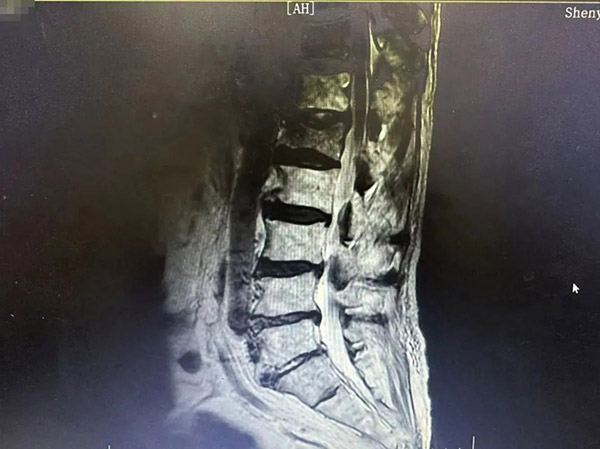

“没事儿,别怕,直起腰,正常走。现在走路是不是不疼了?”